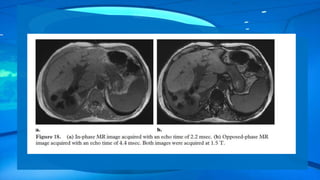

Figure above shows the difference between in-phase and opposed-phase abdominal images

obtained with echo times of 2.2 msec and 4.4 msec, respectively, at 1.5 T. At the in-phase echo

times, the water and fat signals are summed within any pixel that contains a mixture of the two

components, whereas at opposed-phase echo times, the signal in these pixels is canceled out,

leading to the appearance of a dark band at the fat-water interface. In-phase and opposed-phase

imaging sequences are sometimes also referred to as chemical shift sequences.

Figure above showsthe difference between in-phase and opposed-phase abdominal images obtained with echo times of 2.2 msec and 4.4 msec, respectively, at 1.5 T. At the in-phase echo times, the water and fat signals are summed within any pixel that contains a mixture of the two components, whereas at opposed-phase echo times, the signal in these pixels is canceled out, leading to the appearance of a dark band at the fat-water interface. In-phase and opposed-phase imaging sequences are sometimes also referred to as chemical shift sequences.